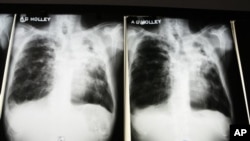

Tuberculosis, or TB, is spread when an infected person coughs or sneezes, dispersing the germ—mycobacterium TB—into the air. The World Health Organization says there were an estimated 8.7 million new cases of TB in 2011. Nearly all TB cases are found in low and middle income countries. People infected with HIV, the AIDS virus, are especially vulnerable because of their weakened immune systems.